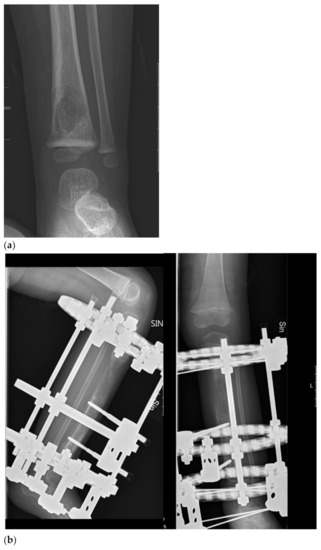

It is well known that ES is a radiosensitive tumor. Initially, surgical treatment was confined to expandable bones, but as surgical techniques evolved, surgical treatment indications extended. Reconstruction with modular and expandable endoprostheses, allografts, endoprosthetic–allograft composites, and vascularized autografts are techniques that have been available for long enough to allow for follow-up over 25 years [88]. These procedures have improved functional outcome and enabled limb sparing surgery [88,89,90,91,92,93,94,95,96]. Recycled autografts and segmental bone transport have additionally improved function, facilitating not only limb-sparing but also joint-sparing surgery (Figure 1) [96,97,98]. Computer navigation, intraoperative CTs, and three-dimensional-printed implants are new tools, especially useful in pelvic surgery, which have further improved accuracy in tumor resection and optimized reconstruction [99,100,101,102,103]. Despite advancements in surgical treatment, complications such as post-operative infection, endoprosthetic loosening, and bone healing difficulties are common in this young and active patient group (Figure 2) [104,105].

Figure 1.

Biological reconstruction using the bone transport technique (a) A two-year old girl presented to the emergency department unable to walk on her left leg after a mild fall 3 days earlier. She also had a fever and a c-reactive protein count of 87 mg/liter. X-ray showing a lytic lesion located centrally in the distal tibial metaphysis of the left leg. There is a relatively narrow, but indistinct zone of transition. Periosteal reaction involving the medial aspect of the tibia was observed. Open biopsy showed a dense proliferation of small round blue cells in hematoxylin and eosin. Immunohistochemistry showed membranous positivity for the CD99 marker; staining was also positive for S-100 and periodic acid–Schiff (PAS). Fluorescent in situ hybridization (FISH) demonstrated an EWSR1-FLI1 fusion transcript consistent with the diagnosis of Ewing sarcoma. Staging procedures did not show any metastases. (b) Induction chemotherapy with VIDE (vincristine, ifosfamide, doxorubicin, and etoposide) was given according to the Euro-Ewing 2008 protocol. Thereafter, physeal distraction, tumor resection, and segmental bone transport with the use of the Taylor Spatial Frame were carried out. The external fixator was removed after 6 months. (c) Five years after removal of the external fixator, the girl is pain free and is able to run and walk without any limitations. Two deformity procedures have been performed after completing oncologic treatment due to a varus deformity secondary to a physeal arrest in the distal tibial physis. She has no evidence of disease.